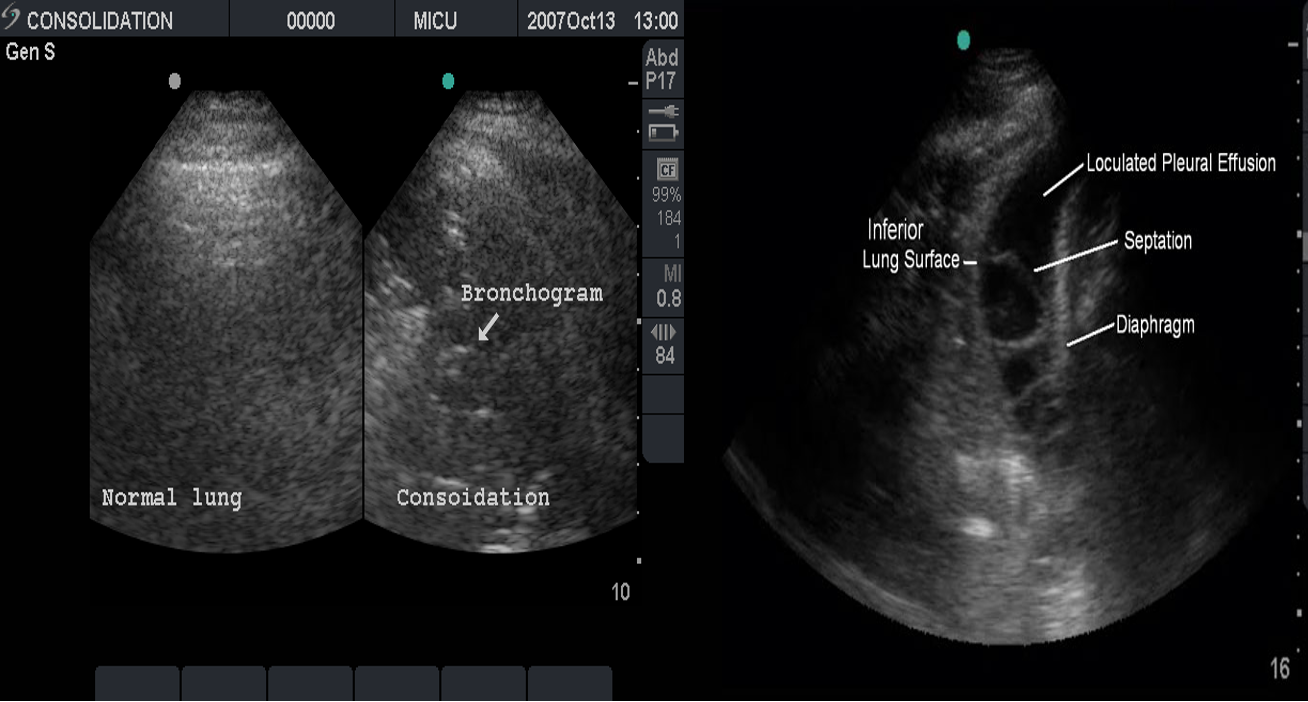

Ultrasound:

This is most useful if a pleural effusion is suspected on CXR. It can differentiate between clear fluid and fibrino-purulent effusions.

Air Bronchogram

Normally, it is not possible to identify air in bronchi within normally aerated lung, because the walls of the normal bronchi are too thin and air-filled bronchi are surrounded by air in the alveoli. However, if the alveoli are filled with fluid, the air in the bronchi contrasts with the fluid in the adjacent lung.